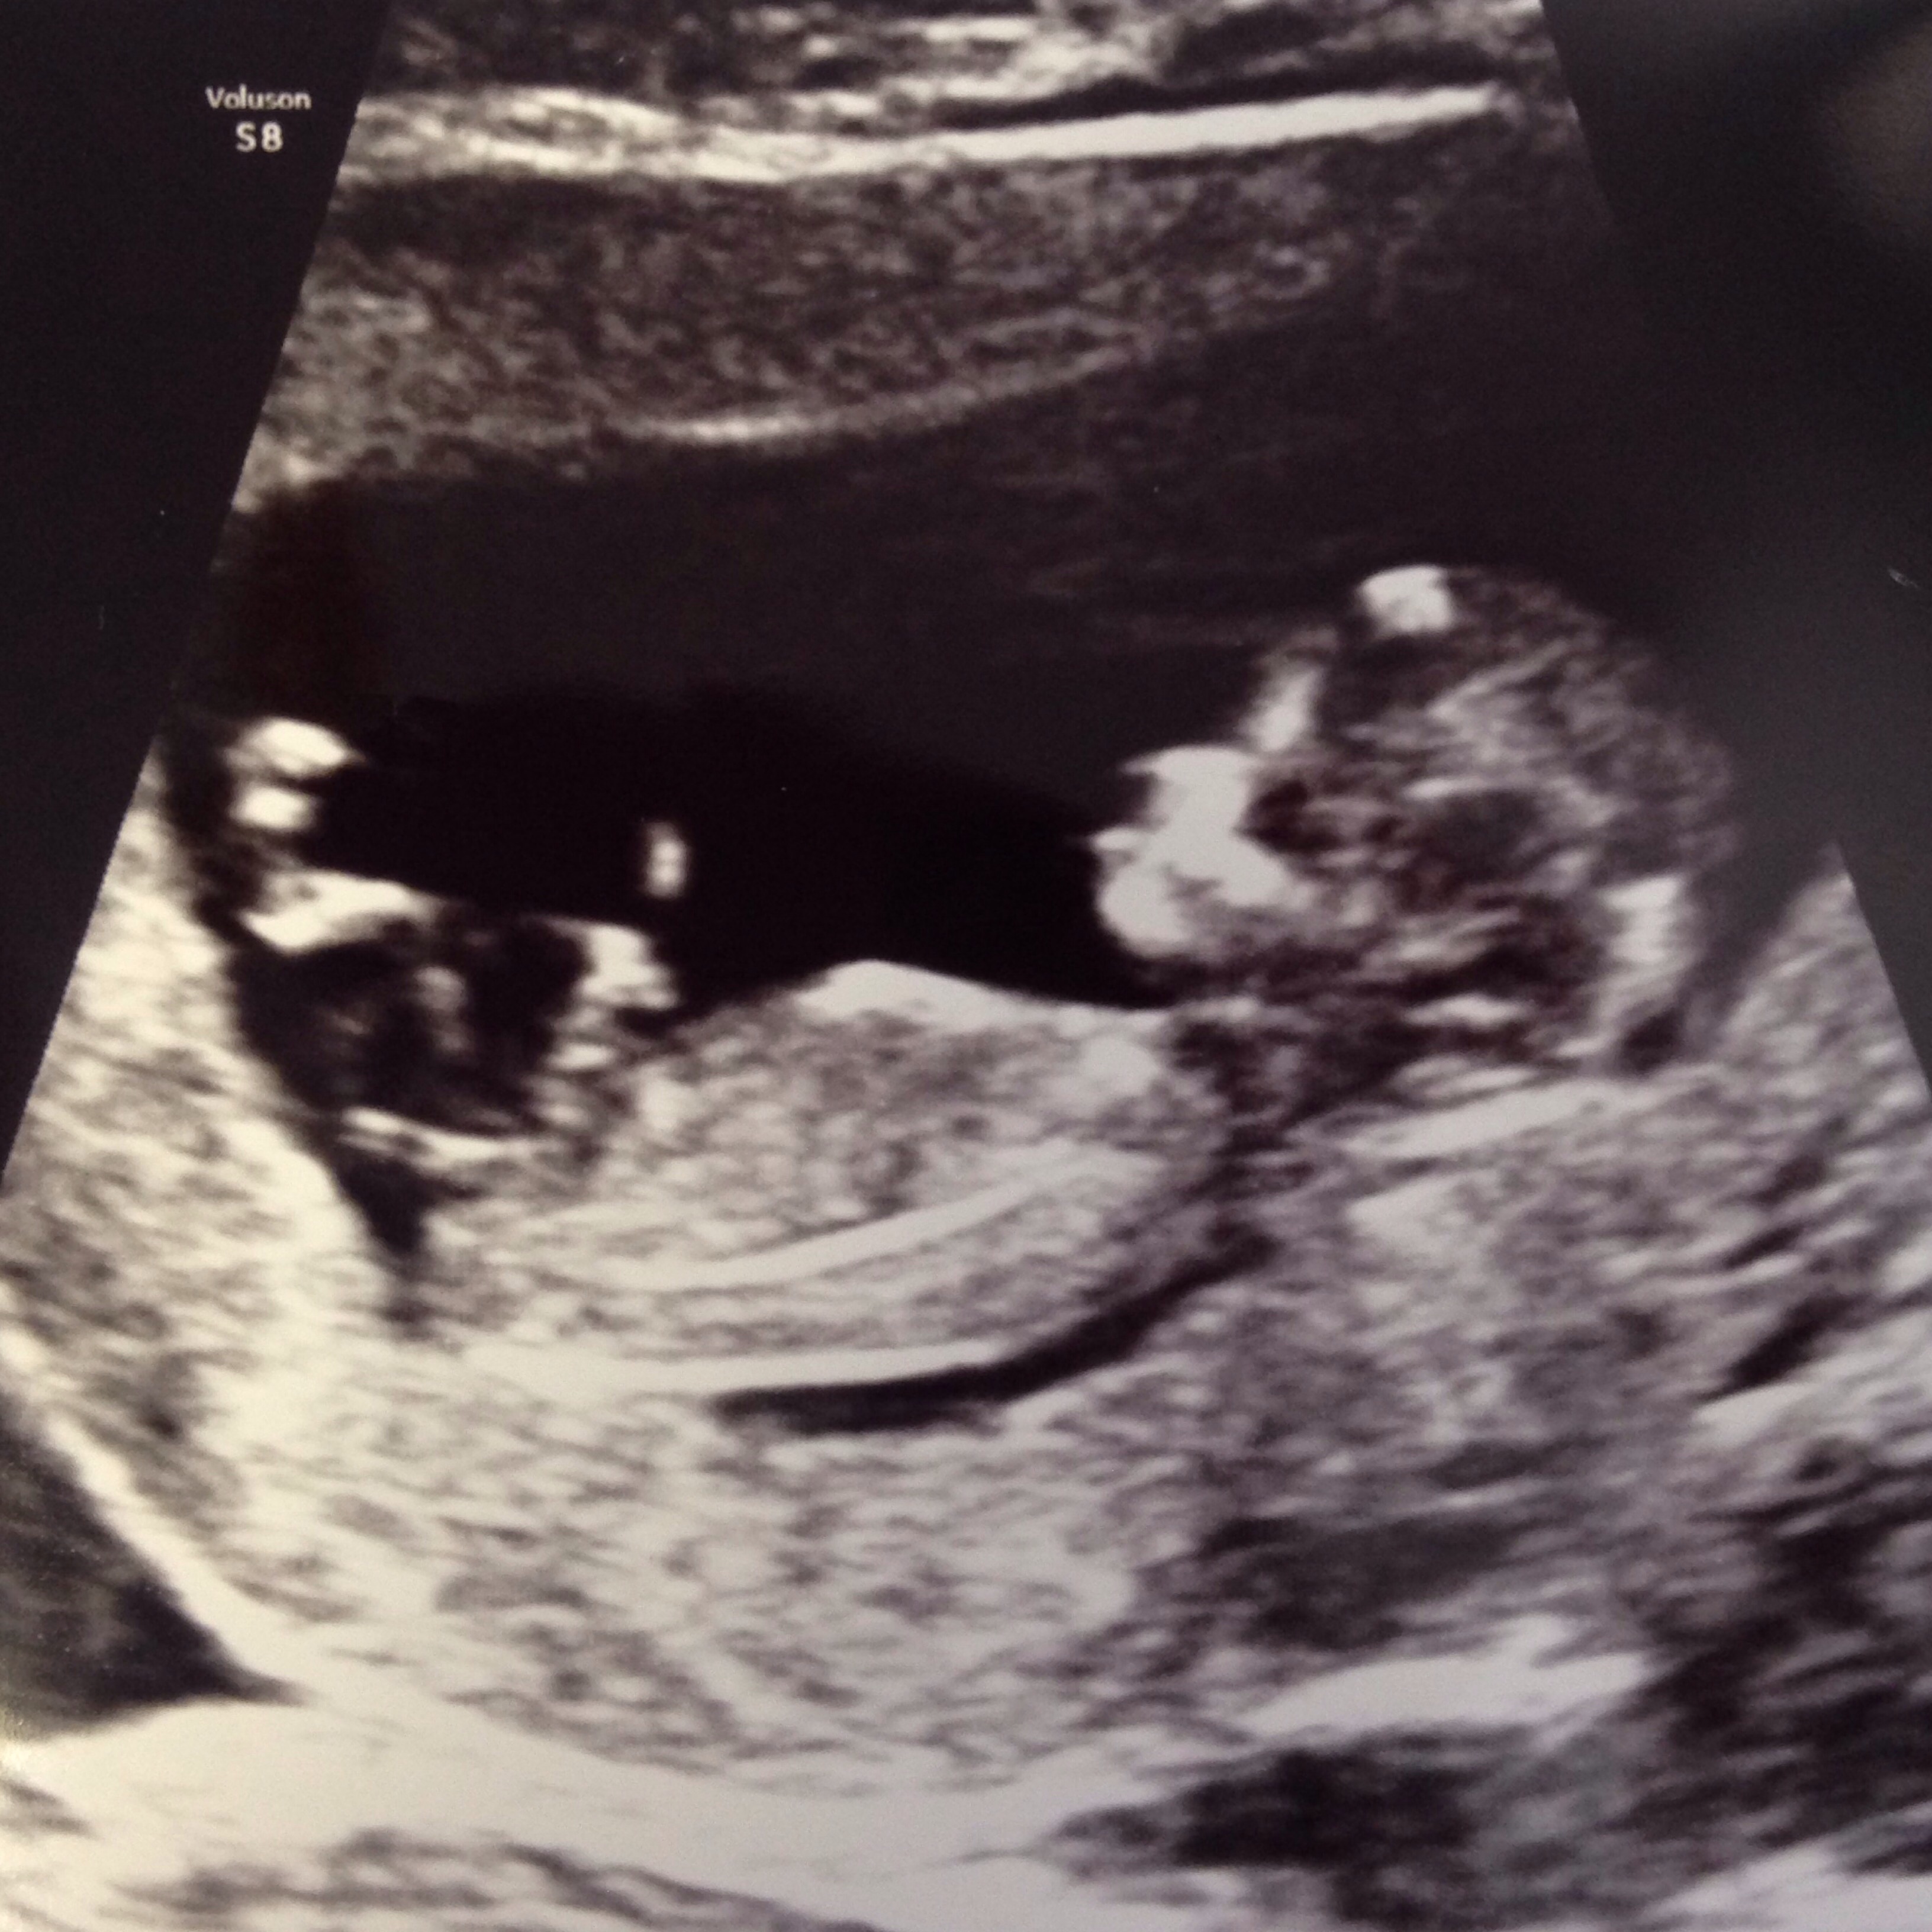

• Had my 12W ultrasound today!!!! Saw the little munchkin - heartbeat and all. 160bpm. . . Saw the measurements written on a paper but don't get actual results for two business days!

• Wow everyone's ultrasounds look so much different from 4 weeks ago.. Looks like an actual baby now! I'll be 12 weeks on Saturday and second appt on Weds so exciting! Can't believe I will be 3 months! Still a little nauseous but I THINK my energy is picking up haven't taken a nap since Sunday I think lol starting to get more of an appetite some days.. Can't wait to announce on social media!